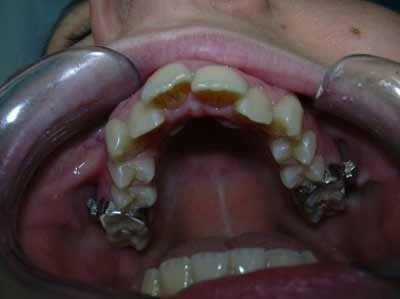

Lo studio dentistico del Dott. Peroni è situato a Flero in provincia di Brescia in via Vittorio Emanuele II, 49. Il Dott. Peroni è specializzato nella medicina chirurgica dentale ed odontoiatrica ed offre i seguenti servizi: Diagnostica, Igiene orale professionale, Restaurativa e Conservativa, Endodonzia, Chirurgia orale, Implantologia, Patologia orale, Ortodonzia, Posturologia, Analgesia Sedativa, Gnatologia, Pedodonzia e Protesi. Presso gli Studi Dentistici del Dottor Peroni ci prendiamo cura dei vostri denti e restauriamo il corretto stato delle vostre bocche. Per fissare un appuntamento con il Dottor Peroni o con i suoi collaboratori è possibile chiamare lo 030 2761577 o scrivere una mail a info@dentistaperoni.it.

Keywords ortognatodonzia, gnatologia, ortodonzia estetica, ortodonzia per bambini, pedodonzia, endodonzia, ortodonzia invisibile, ortodonzia chirurgica, trattamenti di igiene orale, patologia orale, igienisti dentali, sbiancamento denti, pronto soccorso dentistico, chirurgia dentistica, implantologia dentale, dentisti medici chirurghi ed odontoiatri, protesi fisse su denti naturali, analgesia sedativa, endodonzia conservativa, ortodonzia posturale.